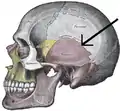

Side view of the cranium. Squamosal suture in red. | |

Side view of the cranium. Squamosal suture highlighted. | |

Parietal bones (above) and temporal bones (below). Side view of the skull. Squamosal suture indicated by the black arrows.

Side view of the skull. Squamosal suture indicated by the black arrows. Close up of left temporal bone. Squamosal suture indicated by the yellow arrows.